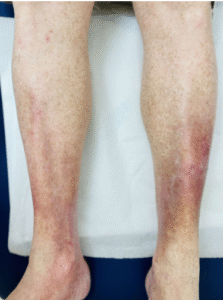

Many people first notice it gradually: the skin around the ankles or lower legs starts to look darker, reddish, brown, or purplish. It’s easy to assume it’s just aging, sun exposure, or dry skin.

Leg discoloration typically starts near the inner ankle and slowly spreads upward. Depending on skin tone, it may appear brown, reddish, purple, or grayish.

What does early venous dermatitis look like?